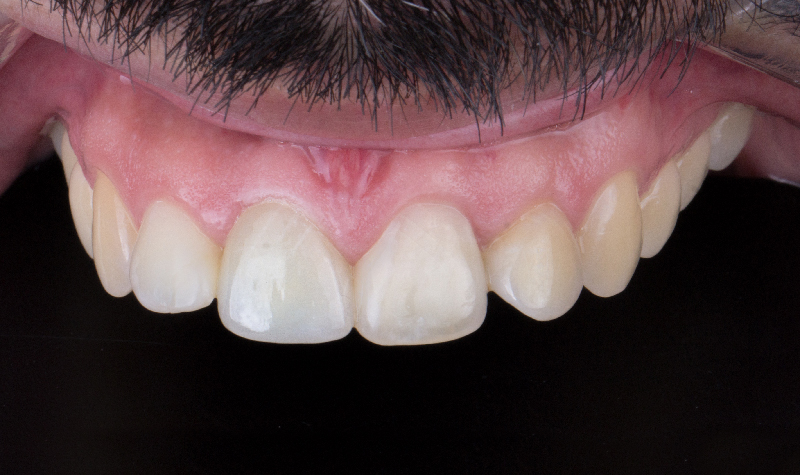

Prótesis híbrida inferior de cerámica fija sobre implantes.

Prótesis híbrida superior de cerámica fija sobre implantes.

Prótesis híbrida superior de cerámica fija sobre implantes